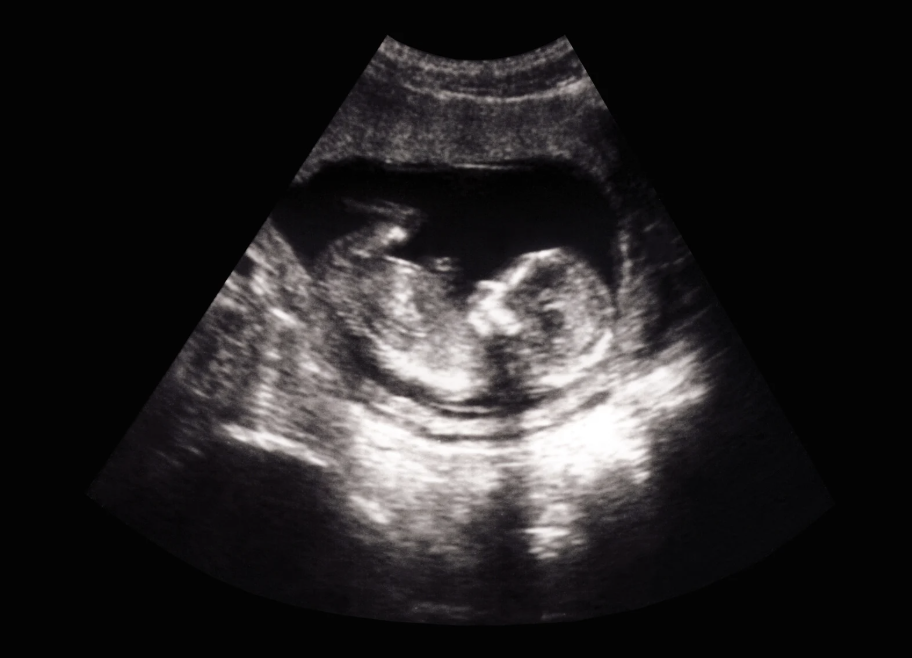

As the ultrasound began, the atmosphere shifted. The screen revealed an active baby, moving energetically, which made it challenging for Kara to capture the necessary fetal measurements. Yet, the lively images brought smiles to Ellie and Jenna’s faces.

Before Ellie left, Aspire Now provided her with ultrasound pictures and connected her with ongoing resources. She stepped off the Mobile Medical Clinic with a smile on her face. Her heart was filled with hope, and she had support from all sides.

Ellie’s story reminds us that behind every ultrasound image lies a turning point. A moment where fear gives way to hope, and one brave choice can rewrite more than one future.